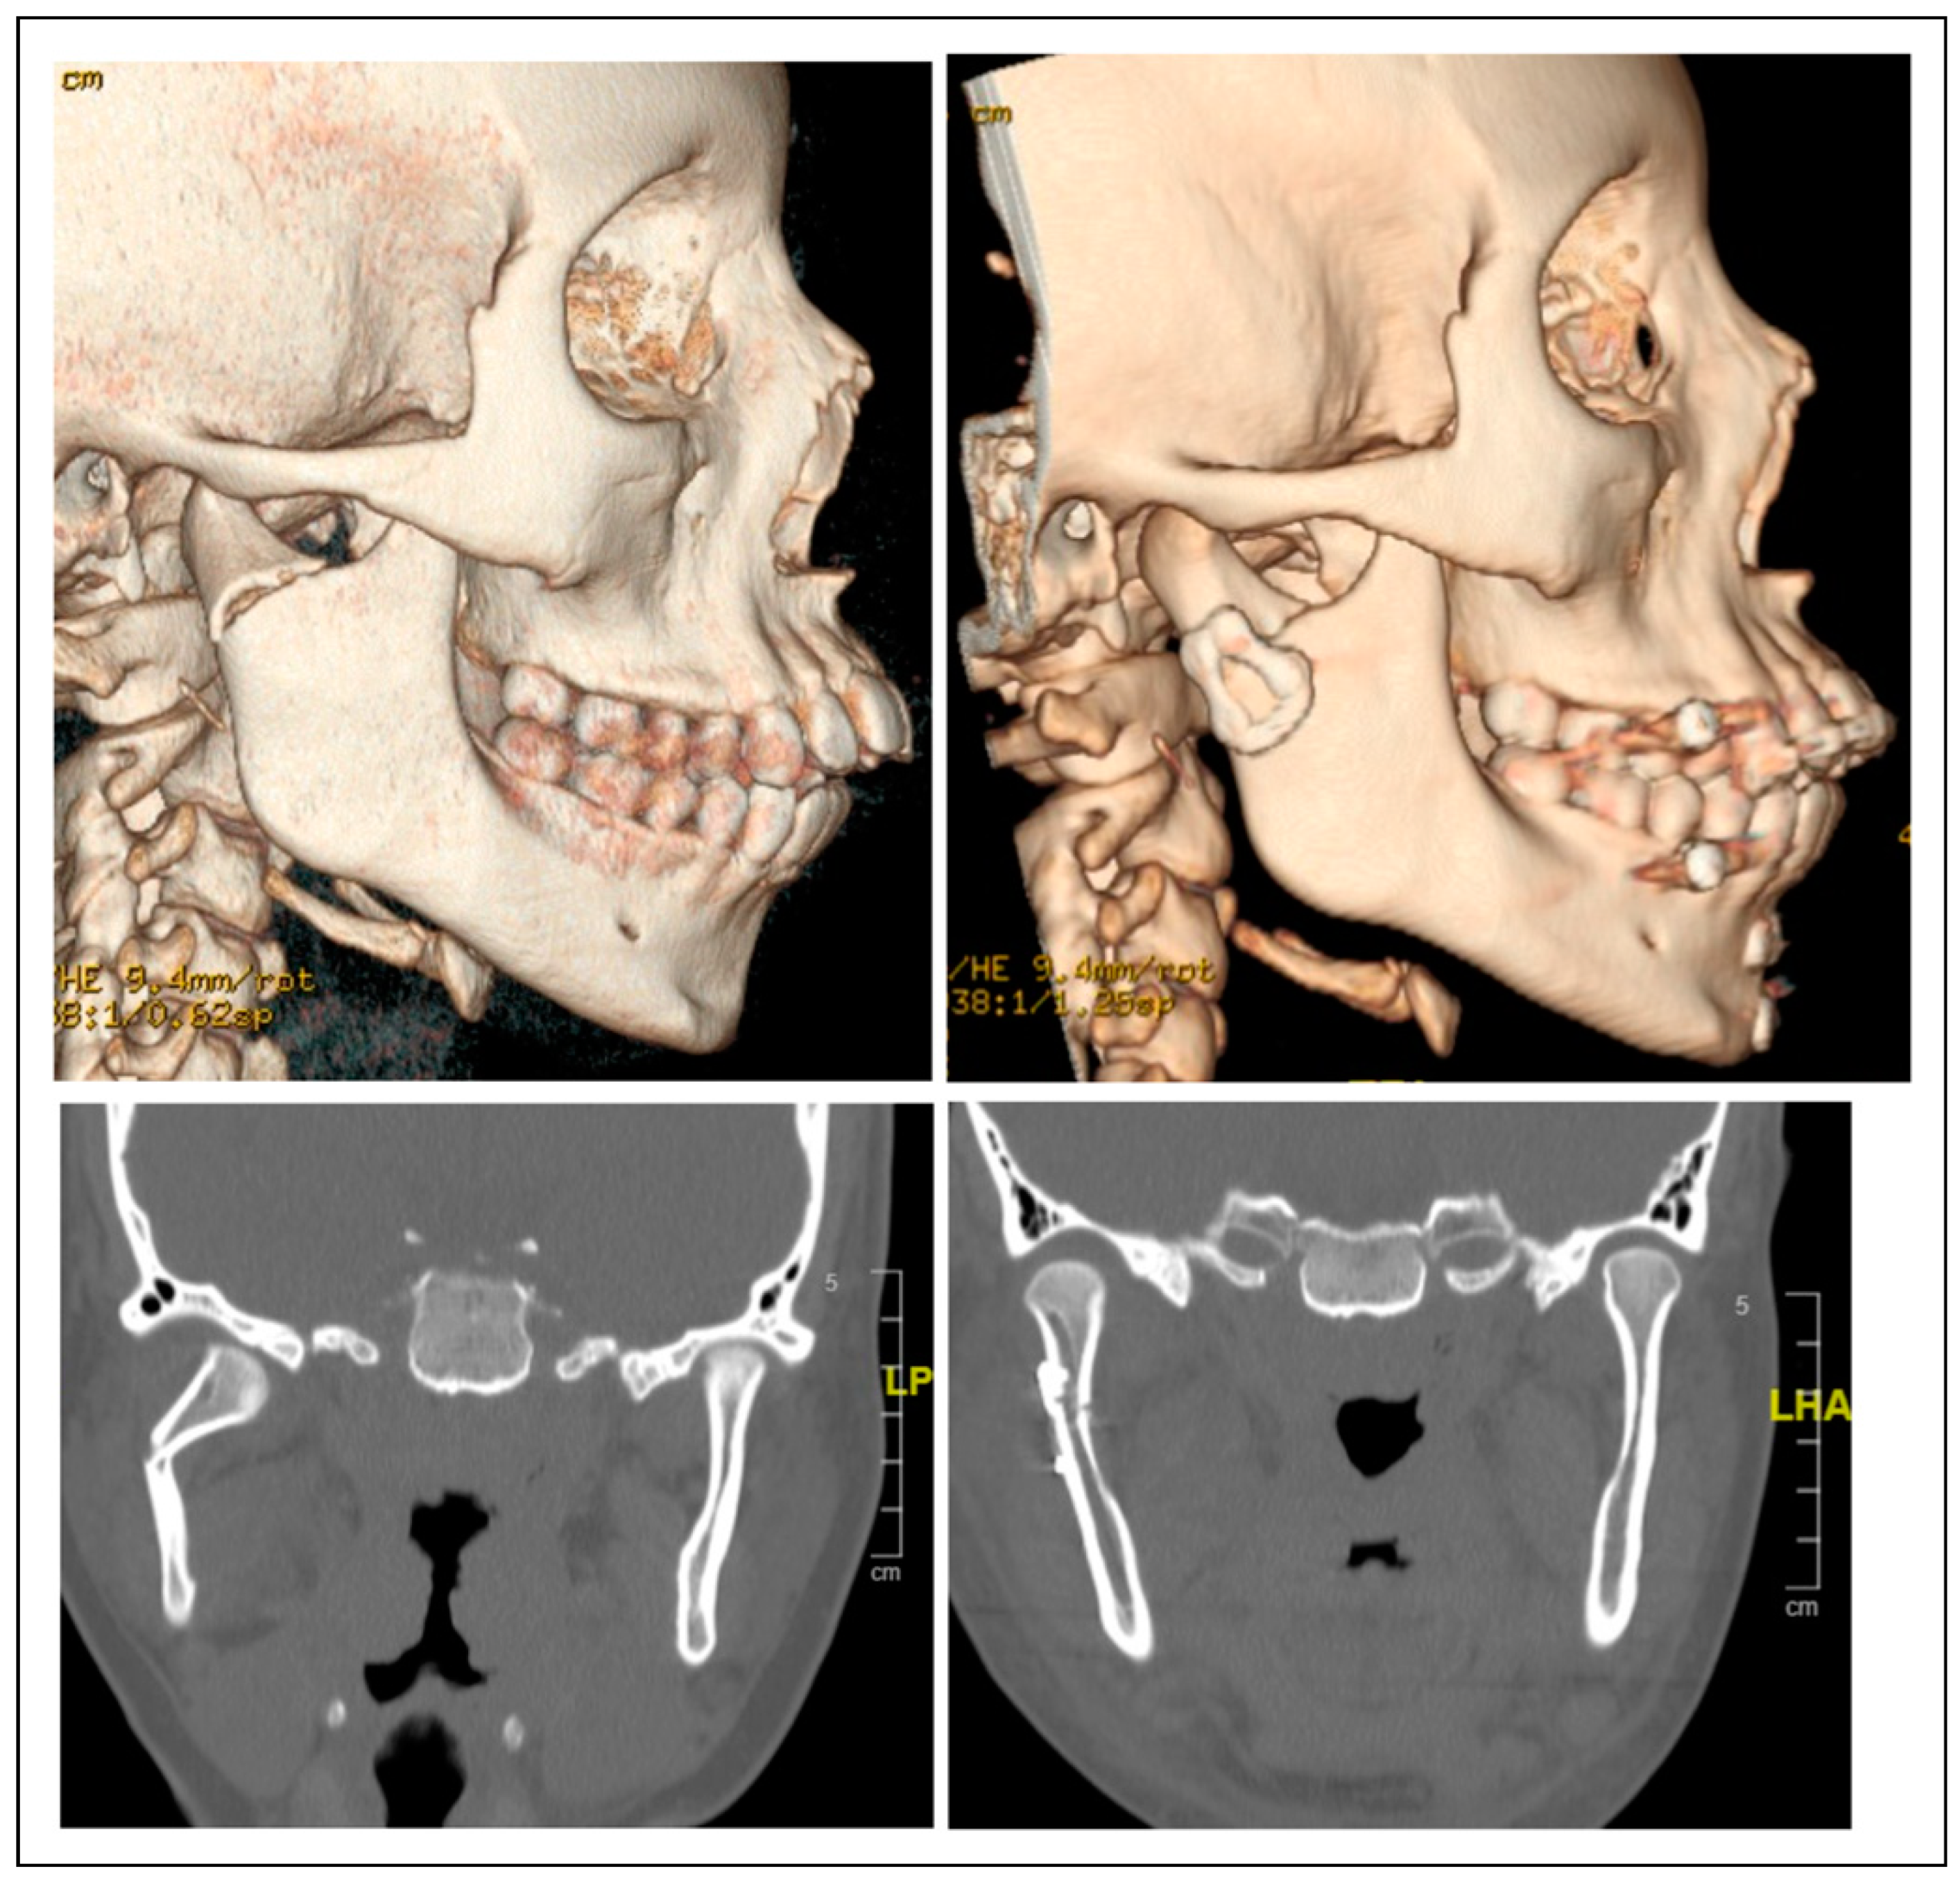

Clinical Experience with a Less Invasive Surgical Transparotid Approach and Trapezoidal Plate for Neck and Base Condylar Fractures: A Retrospective Study

Patients and Methods